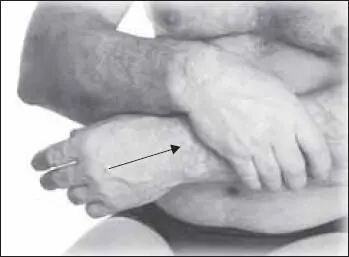

Желательно использовать приемы классического массажа. На области предплечья выполняют обхватывающее поглаживание, все движения направлены от лучезапястного сустава вверх к локтевому суставу (рис. 111).

Также применяют плоскостное поглаживание всей поверхности предплечья (рис. 112).

Кроме того, полезно применять гребнеобразное поглаживание с усилением надавливания к концу движения (рис. 113).

Затем выполняем щипцеобразное поглаживание одной рукой (рис. 114).

Граблеобразное поглаживание широко расставленными пальцами кисти (рис. 115).